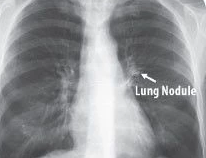

今朝,传统检测办法仍没法发明肺部40毫米年夜小的结节,是以肺癌患者逝世亡率高达90%。欣喜的是,Enlitic开辟的体系能发明小于5毫米的结节,使患者的生计率能增长10倍。

△ 图中箭头所指为肺结节(Lung Nodule)